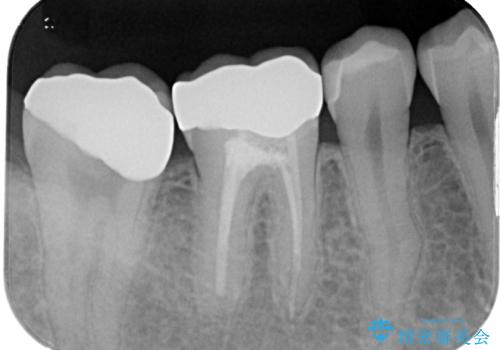

レントゲン撮影を行い、歯髄診査を行いました。歯髄の正常な反応を確認できたのでオールセラミッククラウンによる虫歯治療をすることにしました。

虫歯の上に歯茎が覆いかぶさっていたので、レーザーにて歯茎を除去し虫歯が大きいことが予想できたのでラバーダム防湿下で虫歯の除去をしました。

審美面、機能面共に満足していただけました。

舌側の虫歯が大きかったため歯茎の腫れが心配でしたが腫れもなく経過良好です。